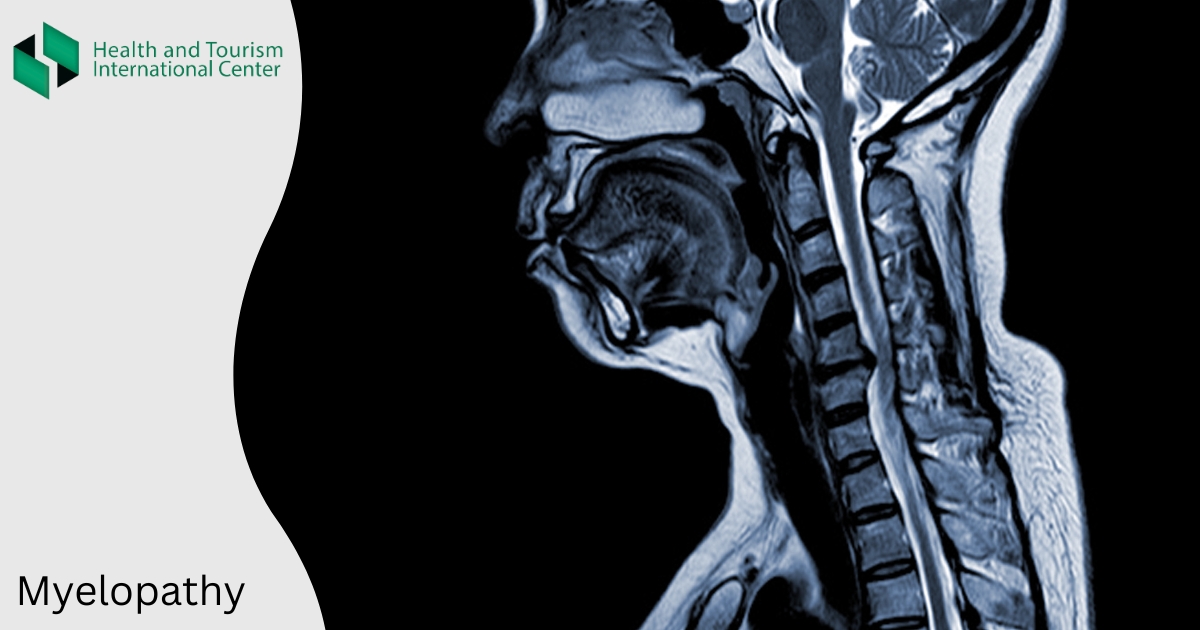

მიელოპათია ზურგის ტვინის კომპრესია, შეკუმშვაა.

- ხერხემლის რენტგენული კვლევა, მაგნიტურ-რეზონანსული ან კომპიუტერული ტომოგრაფია;